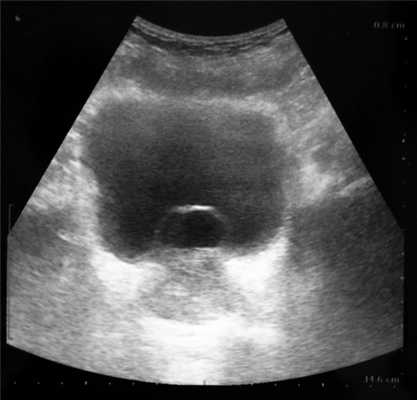

Пациент В., 42 лет, в течение длительного времени отмечал периодическую (1 раз в 4 мес) примесь крови в сперме, однократную примесь крови в моче, умеренное ухудшение качества мочеиспускания. Пациент женат, детей не имеет, в качестве контрацепции применяет барьерные методы. По поводу примеси крови в сперме не обследовался, к врачам не обращался, связывая имеющееся состояние с физической нагрузкой. Из анамнеза известно, что в детском возрасте был поставлен диагноз агенезии правой почки. При прохождении планового медицинского осмотра при УЗИ выявлено образование мочевого пузыря. Учитывая наличие имевшей место примеси крови в моче и сперме врачом-урологом районной поликлиники был поставлен предварительный диагноз опухоли мочевого пузыря. Пациент консультирован в клинике урологии МГМСУ. При трансабдоминальном УЗИ в полости мочевого пузыря определялось округлое образование с четкими контурами, имеющее жидкостный компонент (рис. 4). Рисунок 4. Трансабдоминальное УЗИ пациента В.